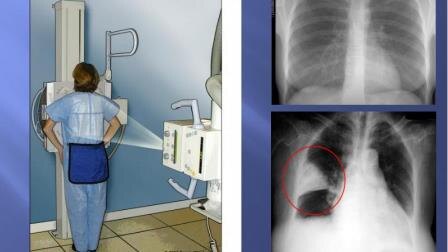

Рентгенологическая диагностика в современной медицине по праву занимает ведущее место среди всех неинвазивных методов исследования. Особое значение она имеет в таких направлениях медицины, как травматология и хирургия. В основе метода лежит прохождение рентгеновских лучей сквозь ткани исследуемой области и последующее отображение их на флюоресцентном экране, пленке или цифровом носителе. Рентгенодиагностика не заменима в исследовании суставов и костей организма человека. Высокая информативность исследования уже более ста лет позволяет определять врачам патологические процессы в костях человека...